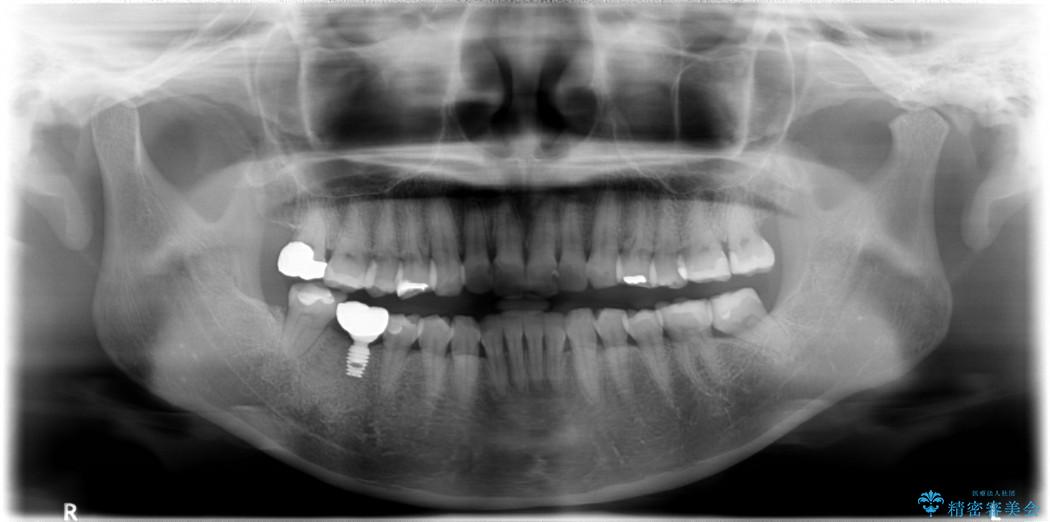

【30代女性】右下奥歯のインプラント 治療例

- 患者様:30代女性

- 治療期間:6ヶ月

- 概算治療費:35万円

他院で右下の奥歯を抜歯しなければならないと言われ、当院へ相談に来られました。

精密な検査を行ったところ、根が完全に折れている為、抜歯が必要となりました。抜歯後は骨と歯茎が痩せてしまう事がないように、人工の骨をつめ、インプラント治療を行う計画としました。

治療後について

抜歯を行った当日に骨の維持をする為、人工の骨を充填しました。インプラントを埋入する際には、ほとんどが自分の骨に置き換わっており、頬舌的なへこみを引き起こす事もなく、審美性・機能性ともに維持する事が出来ました。

また今回の治療では「バイコンインプラント」を使用する事により、インプラントの土台とセラミッククラウンを付ける際にセメントが全く残らないという利点を生かしたところ、見た目にも綺麗に仕上がり、患者様にも喜んでいただきました。